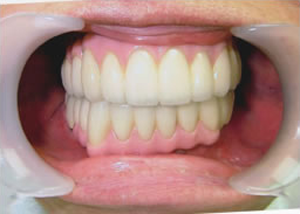

19.下は作った最終本物の歯が入りました。

これで治療終了。

開口器を入れた口元

治療完了

平成21年1月29日

(治療期間:1年7ヶ月)